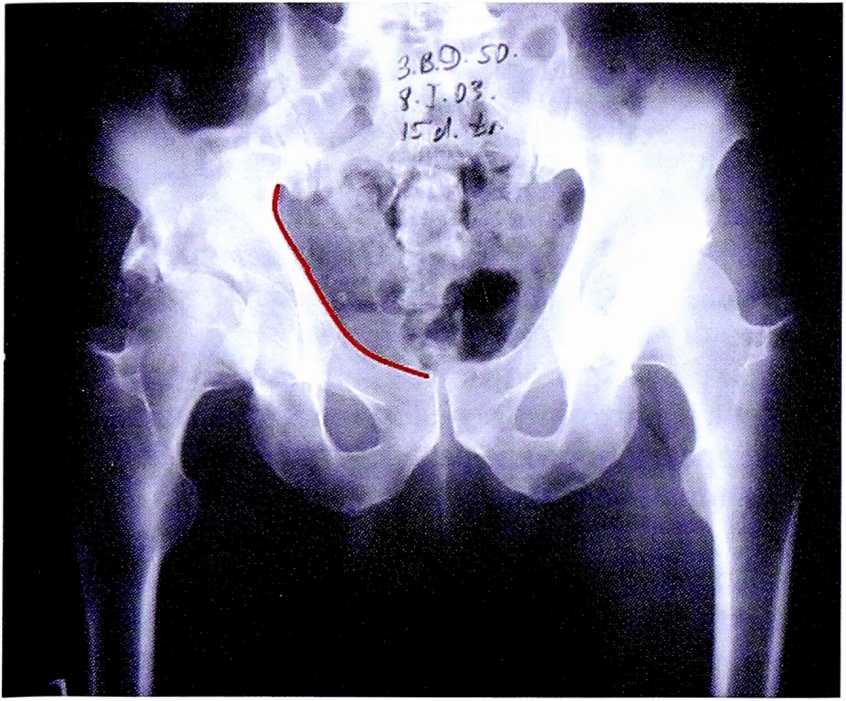

Прямая обзорная рентгенограмма в переднезадней проекции позволяет определить соотношения головки бедра и вертлужной впадины по соответствию стояния головки бедренной кости противоположной стороны (при односторонних переломах), по симметричности линий Шентона. Изменение линии Шентона с большой долей вероятности может свидетельствовать о центральном или краниальном смещении головки бедренной кости, а также о сопутствующем повреждении проксимального отдела бедренной кости. Учитывая индивидуальные особенности тазобедренного сустава сравнение всегда надо проводить с интактным суставом (рис. 8).

Рис. 8. Линия Шентона на обзорной рентгенограмме и на схематическом изображении таза.

Fig. 8. Shenton line on AP pelvic X-ray and on schematic pelvis.